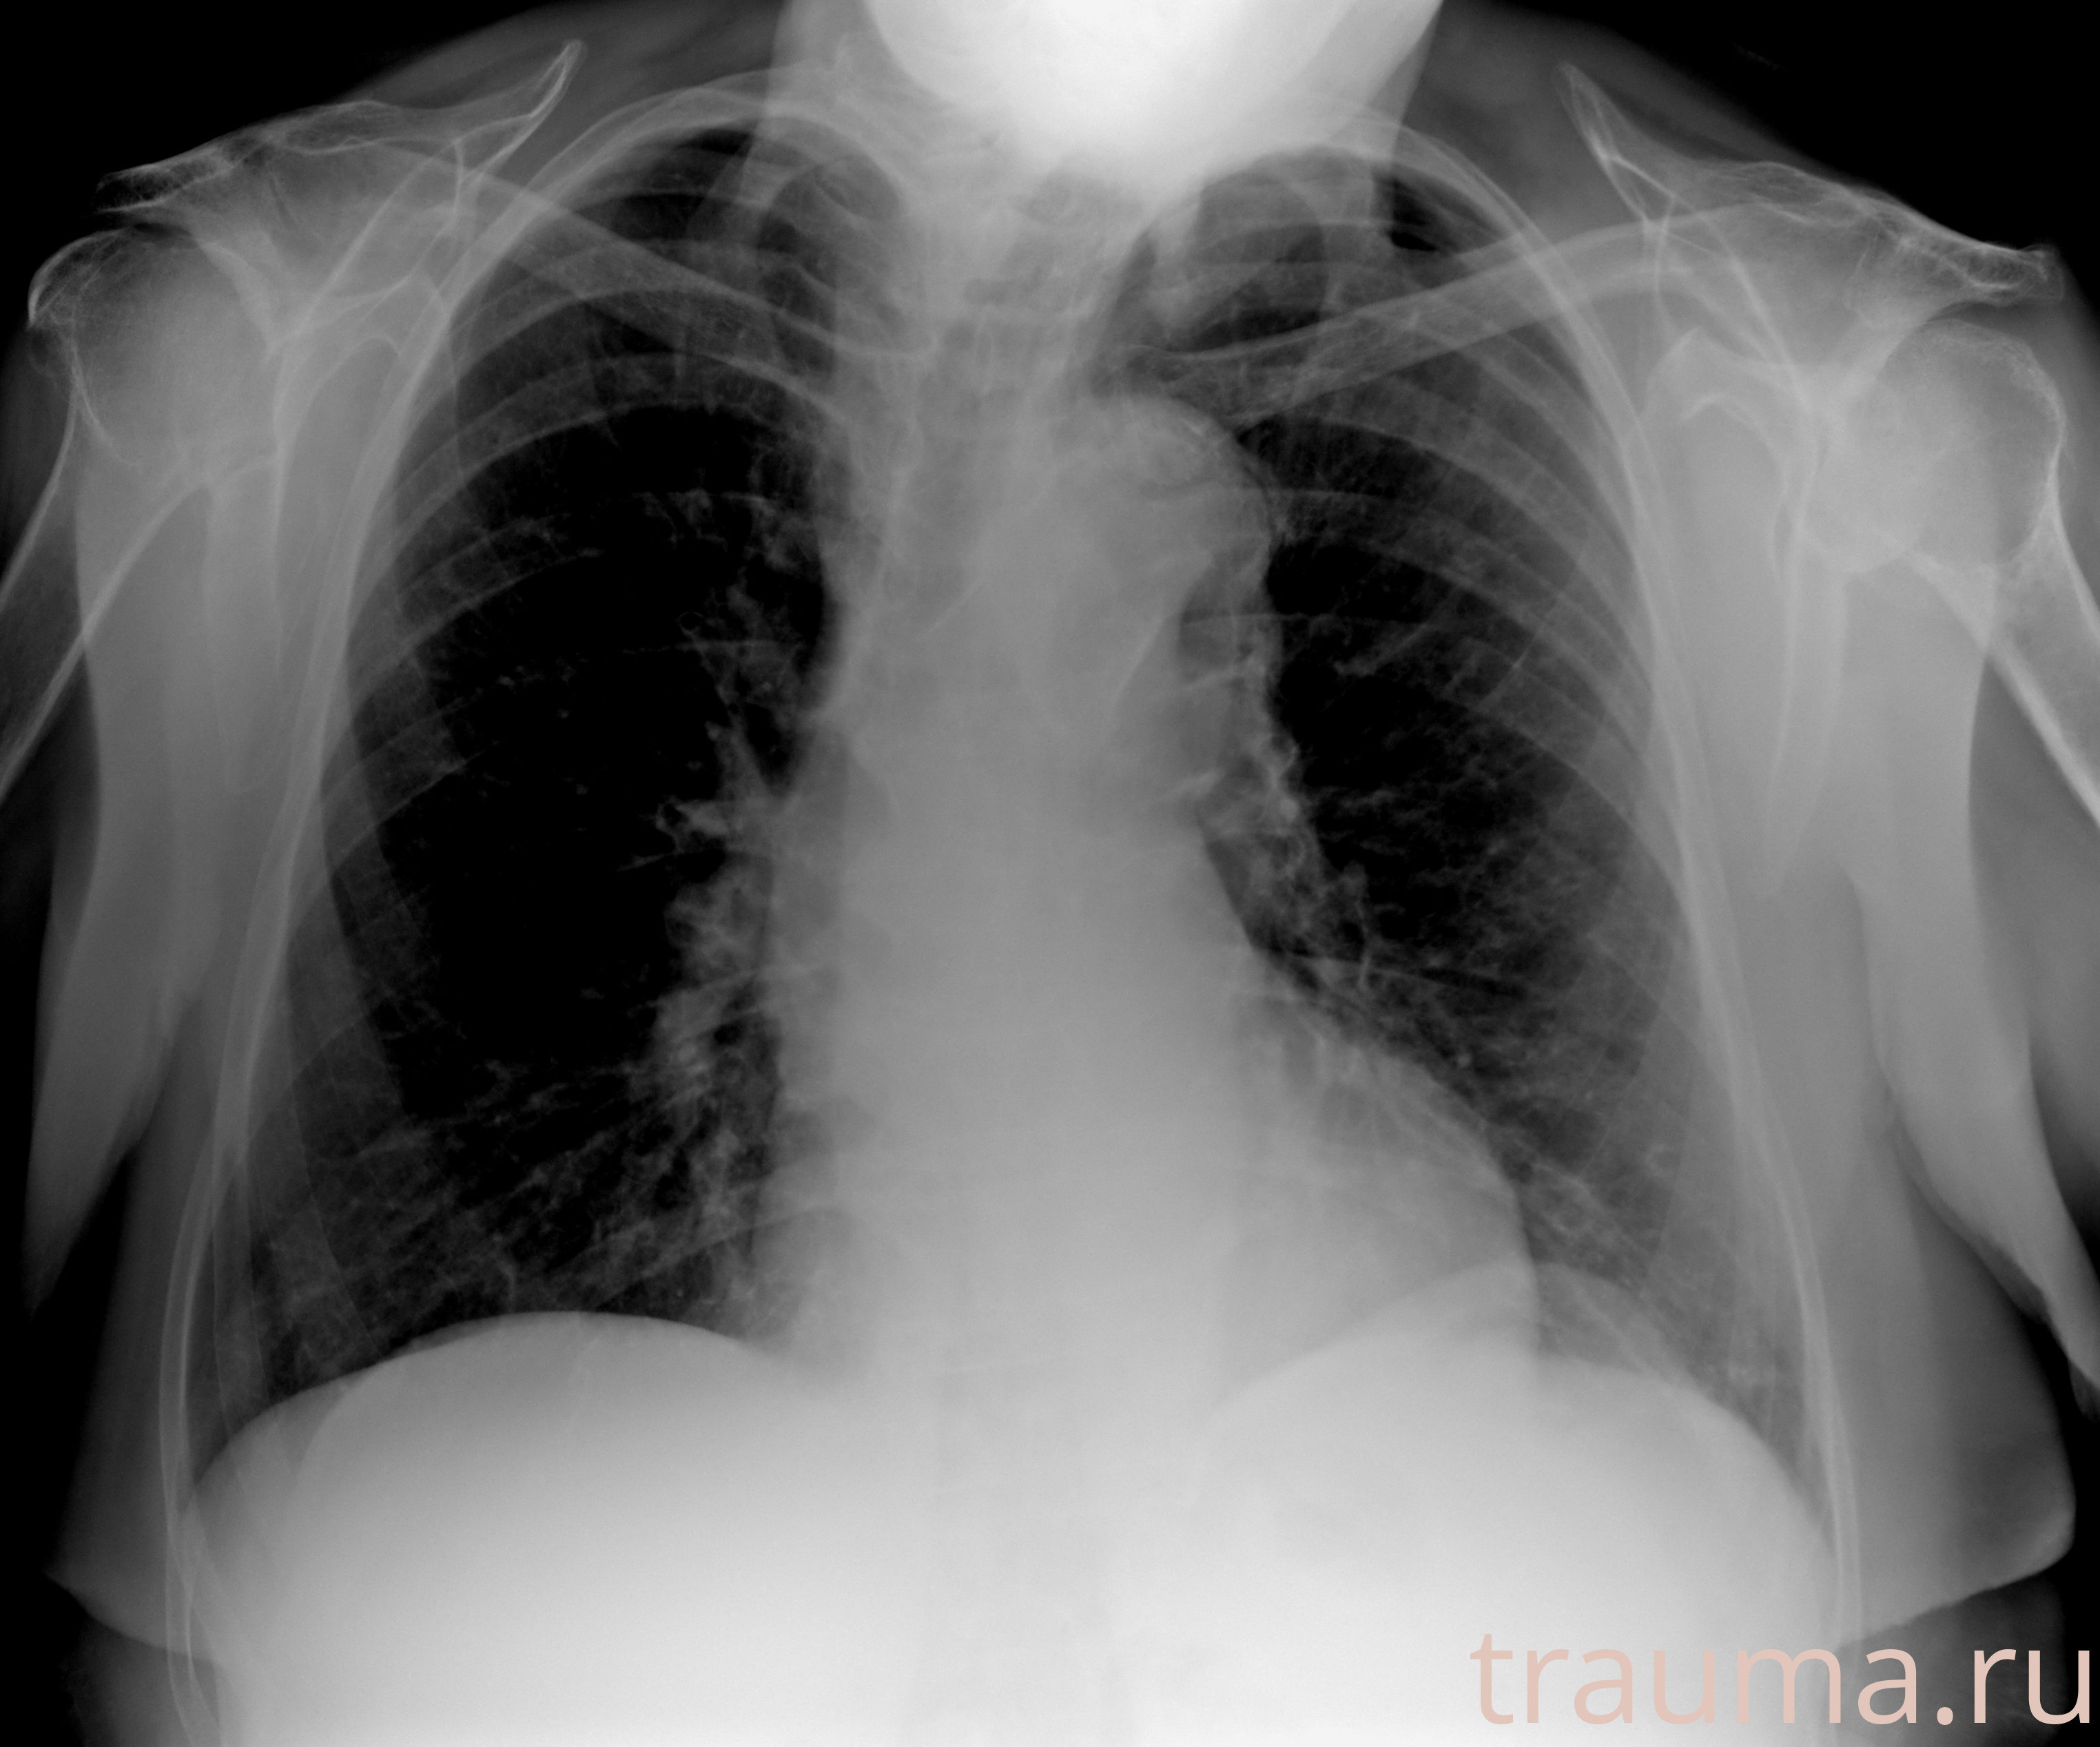

Рентген на дому: по вашему адресу приезжает врач-рентгенолог, травматолог-ортопед с мобильным рентгеновским аппаратом, проводит диагностику травмы или заболевания, делает необходимые рентгенограммы, дает рекомендации по дальнейшему лечению. Получить качественные снимки в домашних условиях возможно благодаря уникальной методике, разработанной МосРентген Центром для института  Склифосовского